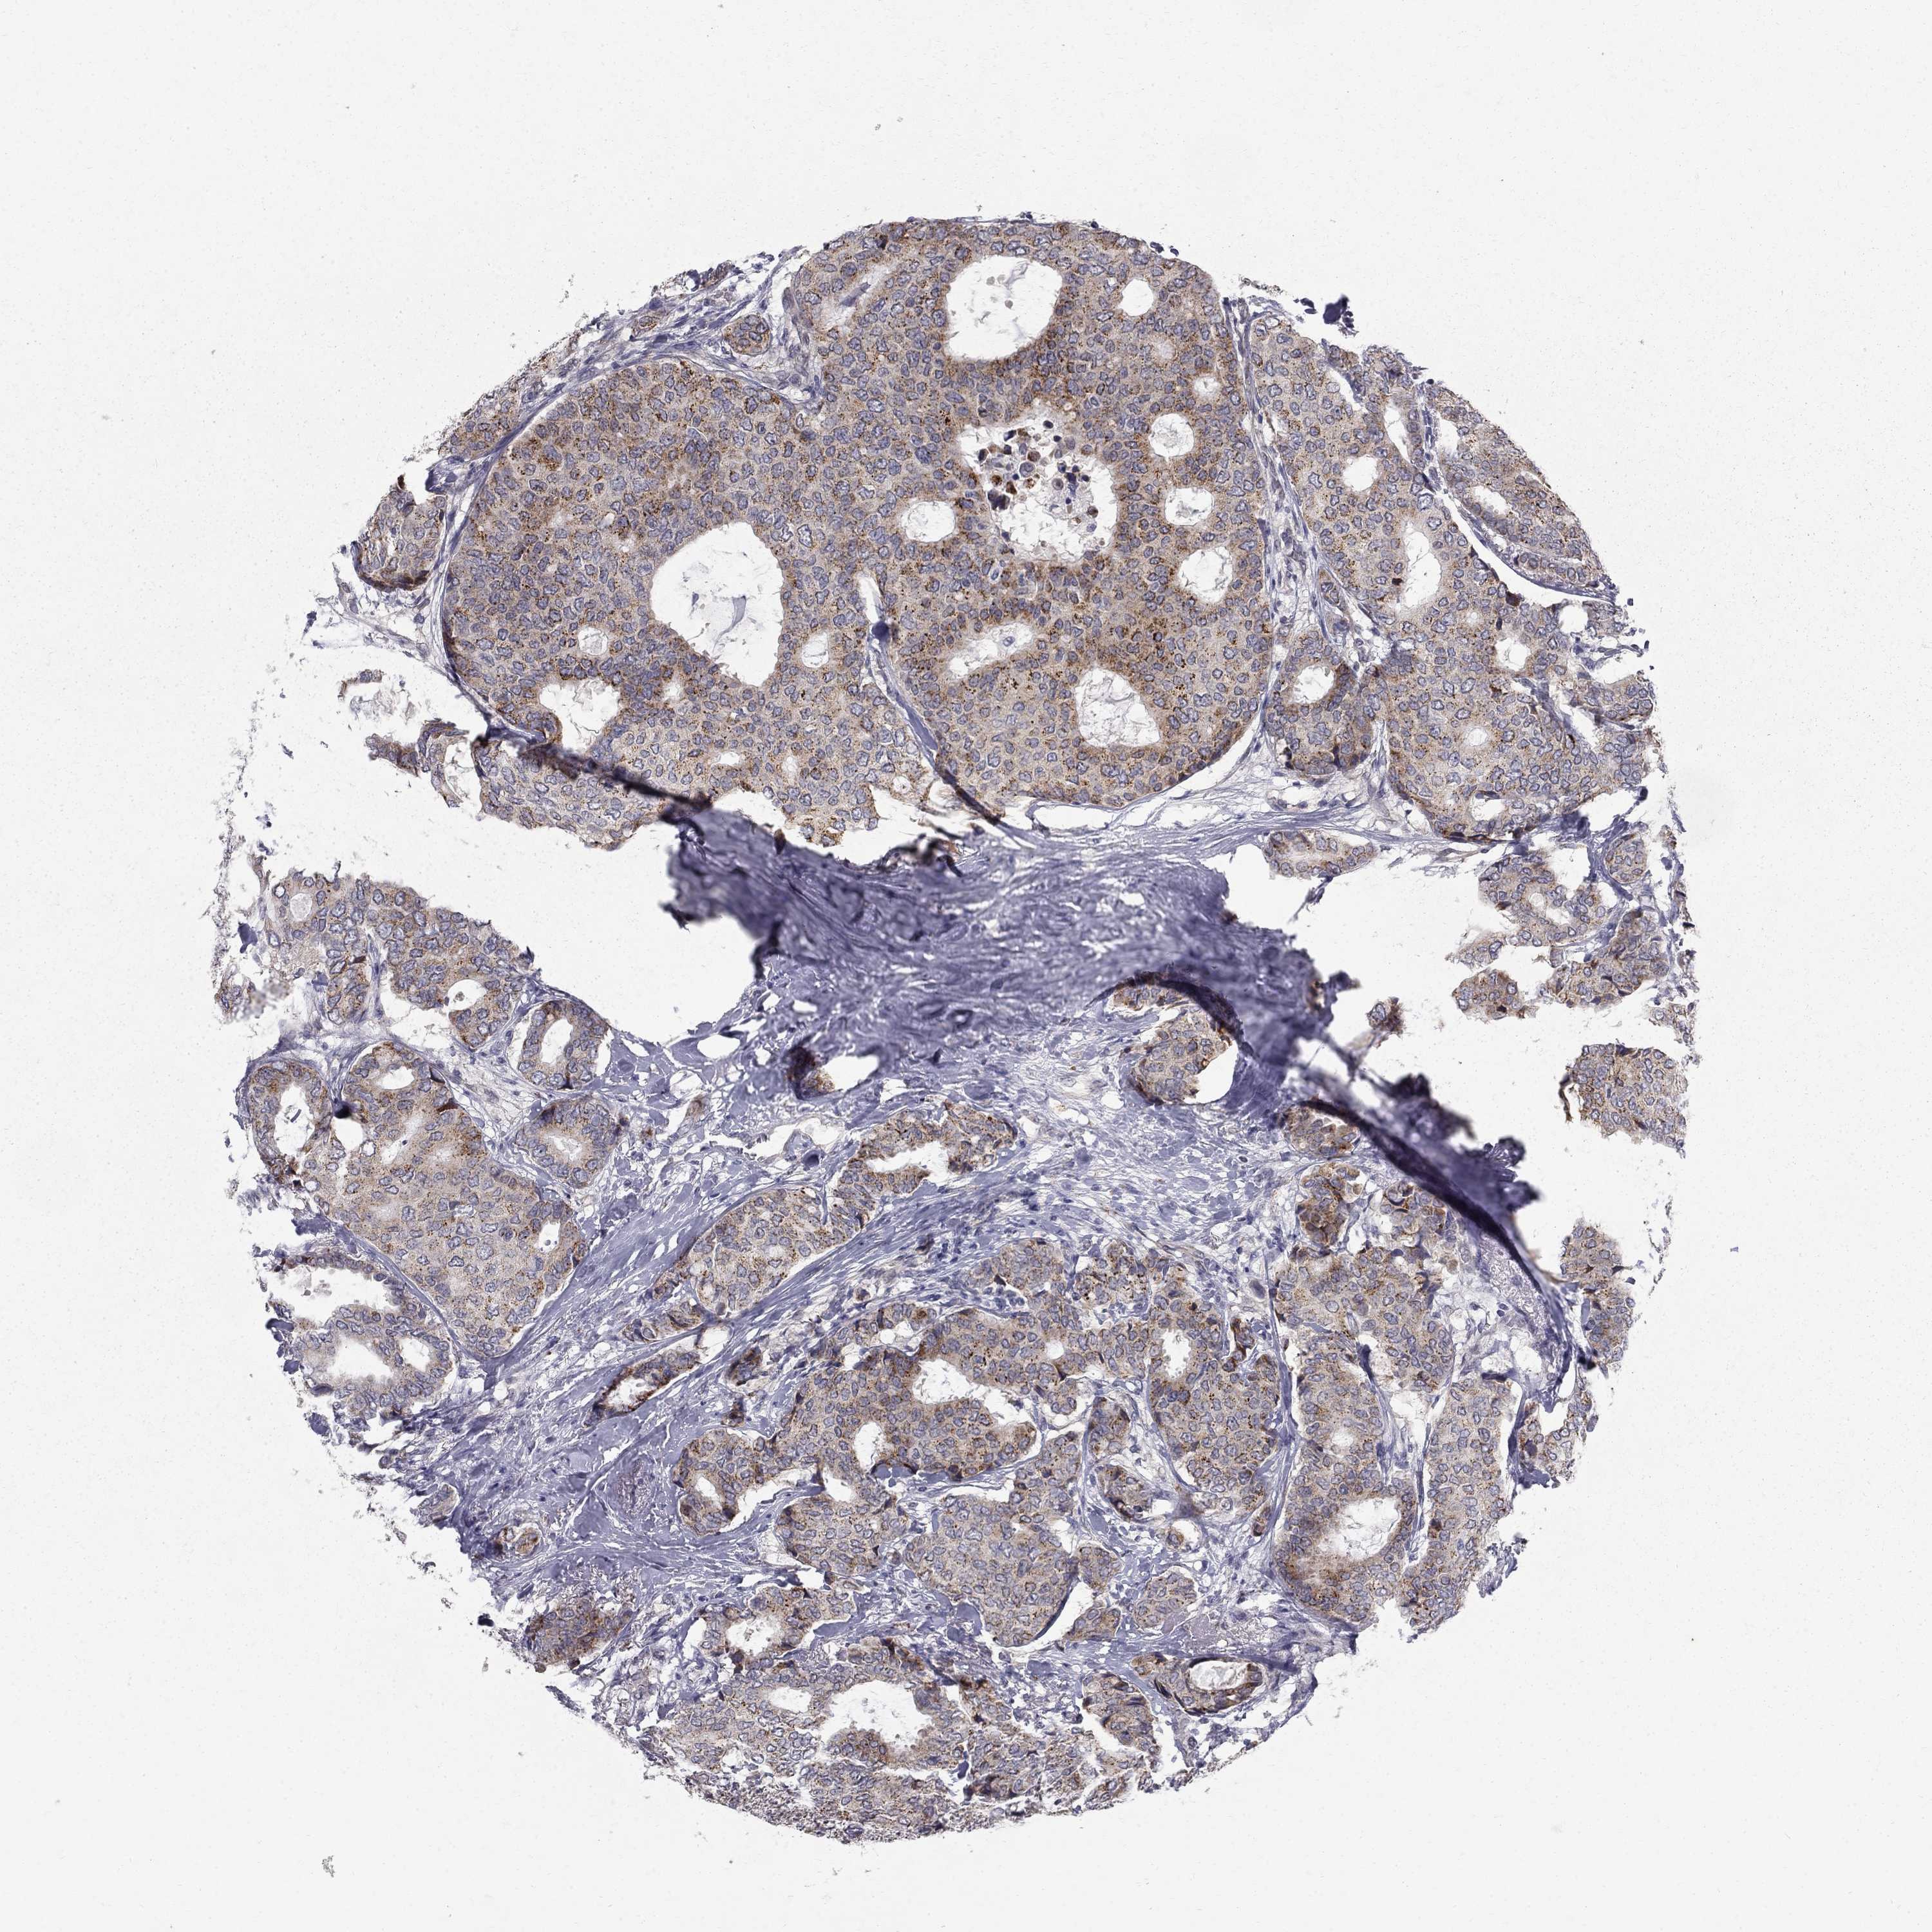

BRCA TCGA BRCA VALIDATION PROTEIN EXPRESSION